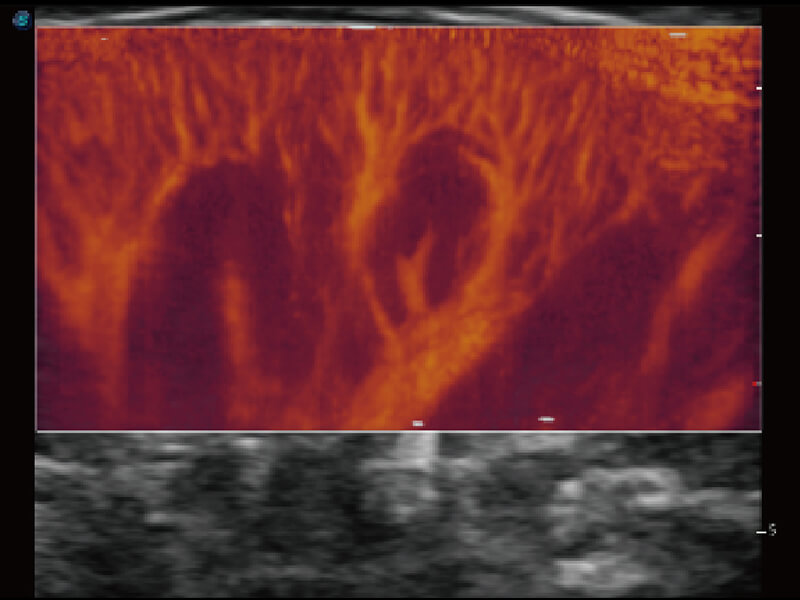

成像功能

性能优异的硬件架构,极大提升超声系统的运行效率和数据处理能力。相比以往超声成像系统,Wis+平台为您带来极快的响应速度和成像帧频,提升检查流畅度。